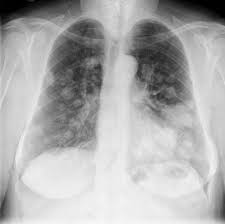

Sekian minggu melakukan percobaan, rontgen pun berhasil mengambil foto tangan istrinya menggunakan sinar x. Menanggapi ramai gerakan pamer foto rontgen ini, ketua perhimpunan dokter paru indonesia (pdpi) dr dr agus dwi susanto, spp(k), menyebutnya sebagai langkah baik. Normal terdapat di sebelah kiri bawah foto rontgen thorak. Tampak gambaran mutiple coin lesion menyebar pada kedua lapang paru. Jadi, kalau memang sangat diperlukan, rontgen ulang dapat. Kardiomegali berbentuk tabung enlemeyer dengan gambaran paru yang bersih merupakan gambaran efusi perikard massif atau tamponade jantung. Cavitas di apex paru dextra fibroinfiltrat dx. Tentu kebutuhan untuk menjalani rontgen sangatlah penting untuk menunjang perawatan kesehatan kita. Rontgen dada juga bisa menunjukkan tulang belakang dan dada, termasuk tulang rusuk, tulang selangka, dan bagian atas tulang belakang anda. Kalau untuk tulang belakang, baru pakai 8 mas, itu baru yang agak berbahaya. Dokter spesialis paru, dr agus dwi susanto, sp.p(k), fisr, fapsr, memberikan apresiasi terhadap para vaper yang telah melakukan foto rontgen. Foto toraks pa deskripsi : Sekian minggu melakukan percobaan, rontgen pun berhasil mengambil foto tangan istrinya menggunakan sinar x. Membahas secara lengkap gejala, ciri ciri, penyebab, diagnosis klasifikasi dan cara menyembuhkan. Radang paru paru disebabkan oleh adanya infeksi virus, bakteri, jamur serta parasit yang masuk ketika sedang bernapas. Besar dan bentuk dalam batas normal, ctr < 50%. Honey comb appearance pd inferior paru dextra perselubungan homogen di paru sinistra.

Source: res.cloudinary.com Namun yang paling tahu adalah dokter yang merawat anda, termasuk masa depan anda. Penilaian yang tepat dan teliti terhadap foto torak memerlukan pengetahuan dan pengalaman yang mendalam. Dokter paru pun angkat suara. Hilus kanan dan kiri normal. Pasien pria, sebut saja a dari china, yang bekerja di pasar makanan laut. Foto rontgen paru dr tirta. Radang paru paru disebabkan oleh adanya infeksi virus, bakteri, jamur serta parasit yang masuk ketika sedang bernapas. Tampak gambaran mutiple coin lesion menyebar pada kedua lapang paru. Terlihat berwarna hitam di seluruh bagiannya (sumber foto:

Source: res.cloudinary.com Menanggapi ramai gerakan pamer foto rontgen ini, ketua perhimpunan dokter paru indonesia (pdpi) dr dr agus dwi susanto, spp(k), menyebutnya sebagai langkah baik. Tampak gambaran mutiple coin lesion menyebar pada kedua lapang paru. Pada foto rontgen, gambaran dari benda padat, seperti tulang, akan ditampilkan sebagai area berwarna putih. Struktur normal dan kelainan pada foto rontgen. Foto toraks pa deskripsi : Menanggapi ramai gerakan pamer foto rontgen ini, ketua perhimpunan dokter paru indonesia (pdpi) dr dr agus dwi susanto, spp(k), menyebutnya sebagai langkah baik. Ukuran jantung yang normal harus di bawah 50% pada foto yang diambil dengan posisi pa dan di konsolidasi paru dapat dilihat dengan memperhatikan perbatasan antara paru dan jaringan sekitar bila terdapat abnormalitas multipel pada foto rontgen, dokter bisa melewatkan kelainan yang tidak. Namun yang paling tahu adalah dokter yang merawat anda, termasuk masa depan anda. Hilus kanan dan kiri normal.